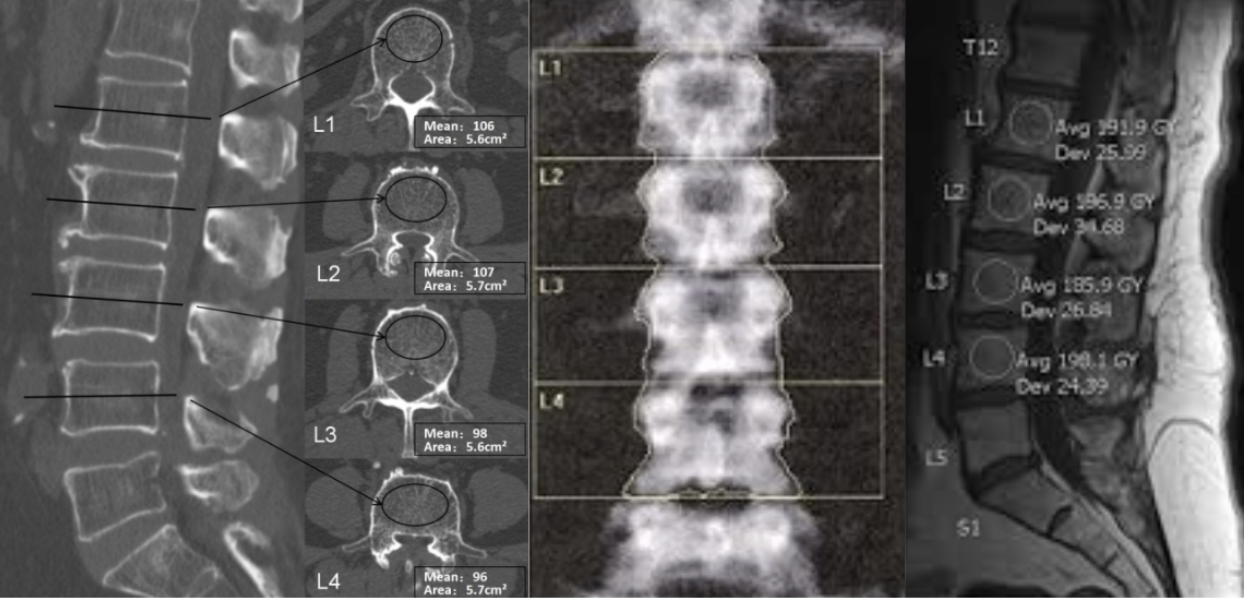

Hounsfield Units (HU)

Hounsfield Units (HU) are a standardized, dimensionless measure of X-ray attenuation on CT, derived from the linear attenuation coefficient (μ) of a voxel relative to water: HU = 1000 × (μ_voxel − μ_water)/(μ_water − μ_air), with water defined as 0 HU and air as −1,000 HU. HU denotes the gray-scale value of each pixel, based on the extent to which the tissue attenuates the X-ray beam relative to water. Within the vertebral body, HU reflects trabecular bone, marrow fat, and, in some cases, cortical shell attenuation. Because trabecular bone is the metabolically active compartment most sensitive to osteoporotic change, trabecular HU within the cancellous centrum serves as an “opportunistic” surrogate for bone mineral density (BMD). Studies show strong links between lumbar HU, DXA BMD/T scores, and mechanical strength, supporting HU as a practical CT-based bone quality measure when DXA is unavailable or unclear.

ROI placement (trabecular centrum technique):

• Use axial images, preferably, and select the mid vertebral body region (about mid-height between endplates) to minimize partial volume effects from endplates and osteophytes.

• Acquire HU from 3 consecutive axial slices centered at mid-body (or the closest available) and average the mean HU across slices.

• Place a large elliptical or circular ROI within the cancellous bone, centered in the vertebral body, targeting trabecular tissue.

• Avoid cortical bone by keeping a margin from the anterior, lateral, and posterior cortical shells (do not contact the cortex).

• Exclude surrounding tissues, different from the vertebral body, and hardware artifacts.

Because HU is scanner-dependent and continuous, thresholds serve as decision-support tools, not definitive diagnostic criteria. Typical opportunistic screening thresholds based on L1 trabecular attenuation are:

• Normal / low osteoporosis risk: >160 HU (high sensitivity).

• Osteopenia risk: 100–160 HU (consider DXA).

• Likely osteoporosis: <100 HU (high specificity).